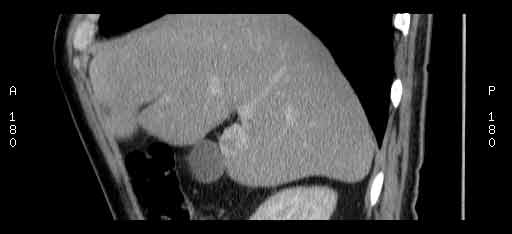

Сонограммы, КТ- артериальная, портальная и отсроченная паренхиматозная фазы

Сделали КТ (весьма похвальная тактика); по КТ: в артериальную фазу: периферическое усиление в виде сливающихся островков контраста, с центрипетальной направленностью. Венозная и отсроченная фаза-хорошее накопление контраста; образование практически изоденсно по отношению к паренхиме печени. Классика гемангиомы. Вуаля-диагноз на "тарелочке".